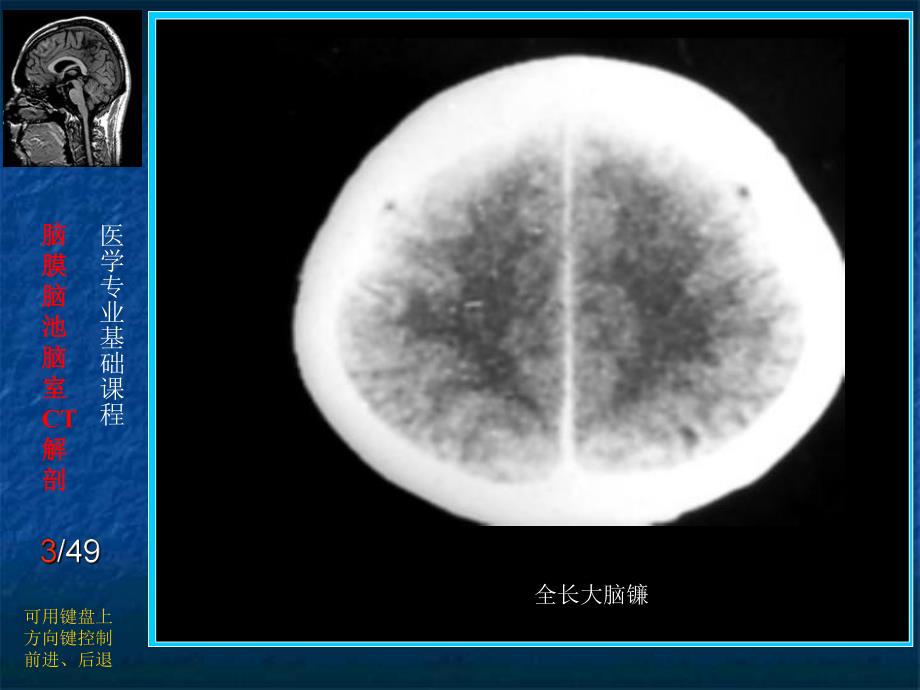

1、脑脑膜膜脑脑池池脑脑室室CT解解剖剖医学专业基础课程可用键盘上方向键控制前进、后退脑脑膜膜脑脑池池脑脑室室CT解解剖剖医学专业基础课程可用键盘上方向键控制前进、后退 上矢状窦中段脑脑膜膜脑脑池池脑脑室室CT解解剖剖医学专业基础课程可用键盘上方向键控制前进、后退 全长大脑镰脑脑膜膜脑脑池池脑脑室室CT解解剖剖医学专业基础课程可用键盘上方向键控制前进、后退 大脑镰前后段脑脑膜膜脑脑池池脑脑室室CT解解剖剖医学专业基础课程可用键盘上方向键控制前进、后退 长Y型小脑幕脑脑膜膜脑脑池池脑脑室室CT解解剖剖医学专业基础课程可用键盘上方向键控制前进、后退 宽Y型小脑幕脑脑膜膜脑脑池池脑脑室室CT解解剖剖医学